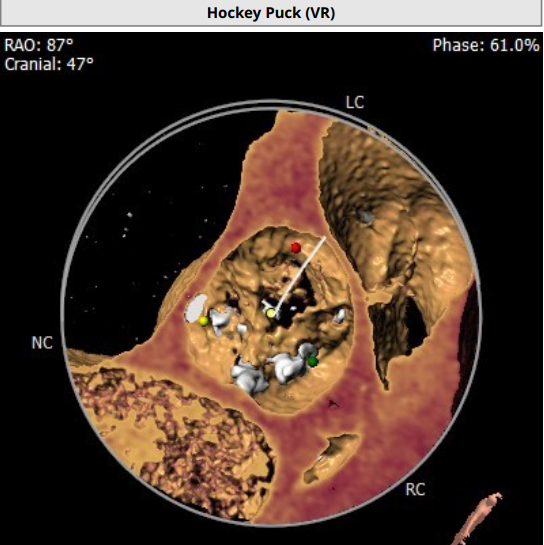

超声心动图显示,主动脉最大流速482cm/s,最大压差93mmHg,平均压差50mmHg,LVEF65%。CT显示主动脉瓣为TYPE2型二叶瓣,严重钙化,右无、左无可见粘连伴钙化,瓣环平面可见钙化,钙化延伸至流出道及二尖瓣前叶根部,左冠高度约12mm,瓣叶长度14.9mm,存在一定左冠风险,法式窦平均直径33.7mm,STJ高度约21.8mm、直径约30.2mm。

主动脉弓部走行较平缓,弓顶部可见少许钙化,主动脉弓部三根毛开口未见明显狭窄征象、未见发育变异,胸主动脉、腹主动脉走行较平直、腹主动脉多发严重钙化斑块,管腔未见明显狭窄,双侧髂动脉-股动脉走形迂曲,双侧髂动脉多发严重钙化斑块,部分呈半环形、马蹄形分布,右侧股动脉可尝试做为主入路,左股动脉作为脑保护入路。虚拟瓣环直径25mm,左室流出道平均直径23.3mm,拟植入VenusA Plus 23/26号的瓣膜。术中balloon sizing确认瓣膜型号,同时确认冠脉风险。